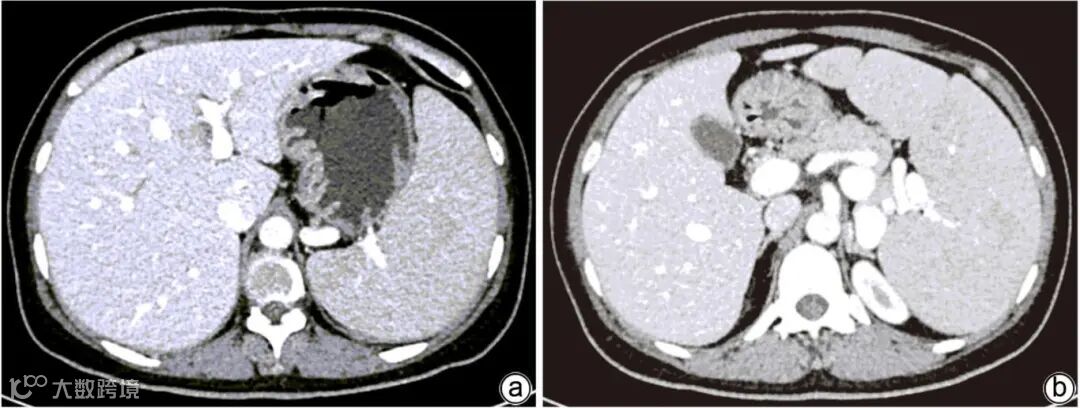

注:a,脾脏肿大;b,肝脏肿大。

图2 上腹部CT平扫

注:a,门静脉扩张,门静脉高压;b,脾静脉增宽迂曲,脾肿大。

图3 腹部增强CT+门静脉CT血管造影

NPD-B是一种由编码鞘磷脂磷酸二酯酶-1的SMPD1基因突变导致的常染色体隐性遗传病,发病机制为酸性鞘磷脂酶相对缺乏,不能将鞘磷脂水解为神经酰胺,造成过多的酸性鞘磷脂在患者全身的网状内皮细胞中贮积而致病,临床上以肝脾肿大多见,部分患者伴有肺部浸润,无神经系统症状,大多可活至成人。肝脾肿大是该病大多数患者初诊的原因,肝肿大的程度可达正常时3倍,肝脏触诊质地偏硬,如橡胶状,边缘欠光滑。除了脂质巨噬细胞在脾脏网状内皮系统堆积外,肝脏肿大伴门静脉高压对脾脏肿大有叠加作用,因此,脾脏肿大较肝脏肿大更突出,部分患者脾脏体积可约达正常时28倍,也有脾梗死和脾破裂的报道。本例患者腹部查体发现肝脏和脾脏均肿大,腹部影像学检查提示肝脾大,门静脉、脾静脉增宽等门静脉高压征象,符合NPD-B常见的临床表现。NPD-B患者的肝生化学检查通常为转氨酶轻度升高,以AST升高多见,升高程度多为正常值上限1~2倍。TBil水平也轻度升高,在年长者数值更高。对29例NPD-B患者长达10年随访的一项研究表明,急剧大块的肝细胞坏死是罕见的,随着时间推移,各生化指标大多会保持平稳,仅少数缓慢上升。虽然肝生化学指标大多数为轻度异常,但肝脏病理学改变是多样化的,富含鞘磷脂的泡沫细胞在肝脏中广泛存在,除Kupffer细胞外,还可累及肝细胞、胆管上皮细胞和血管内皮细胞。有报道,中央静脉周围肝细胞肿胀、有细小空泡状细胞质,还可观察到泡沫状组织细胞浸润纤维间隔,而炎症细胞在肝组织中却不常见,部分患者可有轻微纤维化、进展性桥接纤维化,甚至假小叶形成,提示该病可进展为肝硬化。在酸性硝磷脂酶基因敲除的NPD模型小鼠中发现,组织蛋白B过度表达,从而促进肝纤维化,这与临床肝纤维化、肝硬化的表现相一致。有死于肝衰竭患者尸检显示,肝血窦淤滞,被富含脂质Kupffer细胞完全阻滞,可伴机械性溶血的现象。因此,肝生化学指标并不能全面反映NDP-B病情的严重程度,需结合临床症状、脏器功能、病理和影像学检查等全面综合评估。本例患者因脾功能亢进,PLT计数波动在30×109/L~50×109/L,肝穿刺有潜在出血风险,故未行肝穿刺检查。